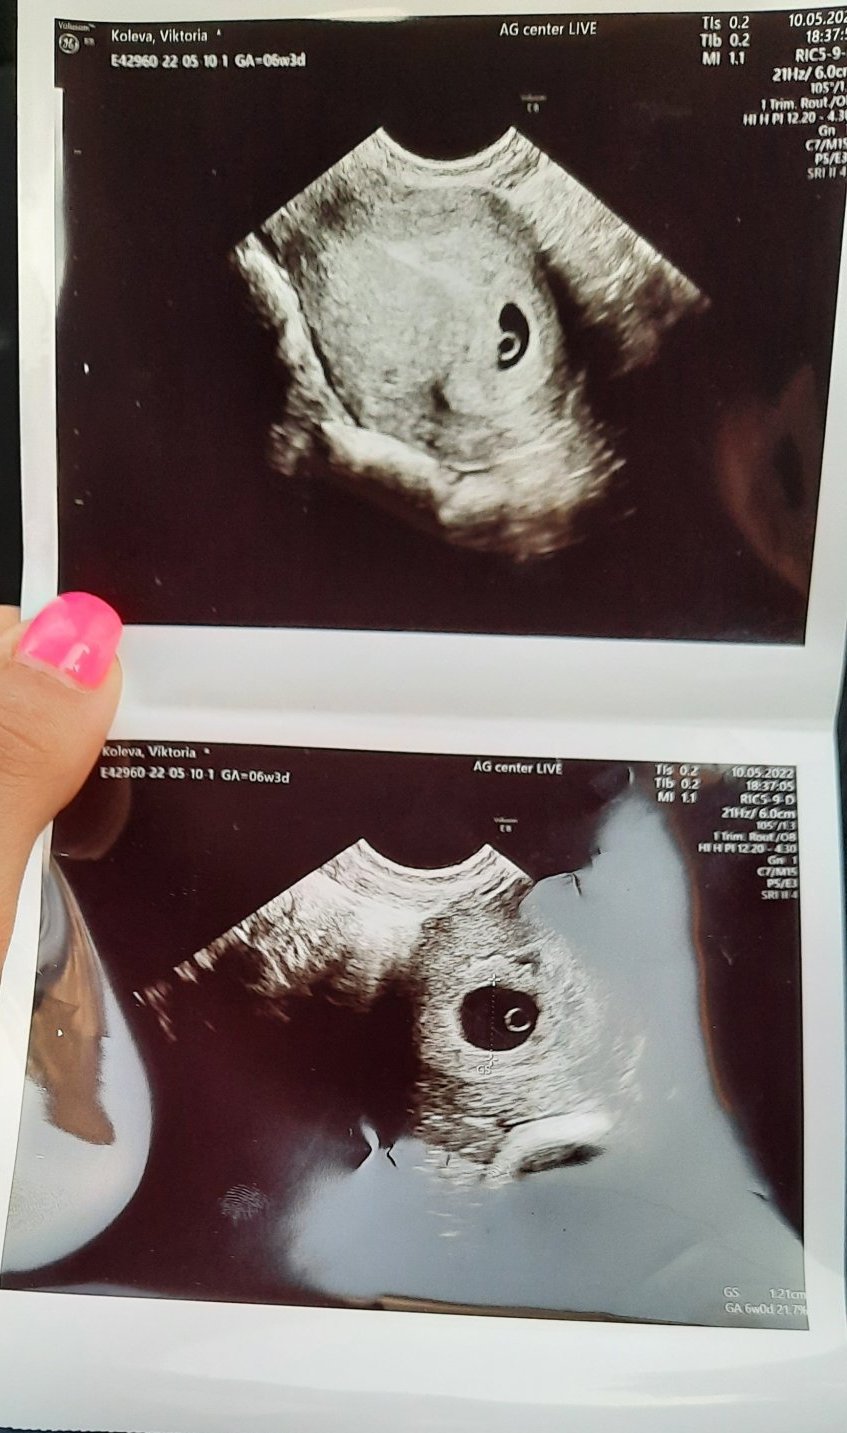

Здравейте на 10.05 бях на преглед при Аг видяме на видеозон (вагинален ) и видя цитирам "мехурче от което се храни бебето" или нещо такова бяхразвалнувана на 25ти отново съм на преглед да чуем сърдечен ритам ,каза,че щв ни каже честито когато чуем сърдечен ритъм иначе ми регистрира бременноста т.е височина сегашно тегло и как ще раждам и термина на 3януари ,Но не каза в коя г.с седмица съм имам снимка дали може да ми кажете вие 😁,ще прикача снимка ( забравих да питам аг)

6та седмица и 3 дни пише (6w3d). горе вляво.

Оф да много се извинявам гледах ,гледах какво съм гледала 😒.Благодаря Ви !❤ А нормално ли е да не чуваме сърдечен ритъм на бебето или е рано?

Не при всички се чува 6та седмица, вече ако и в 8ма не се чуе е подозрително... Стискам палци Simple Smile